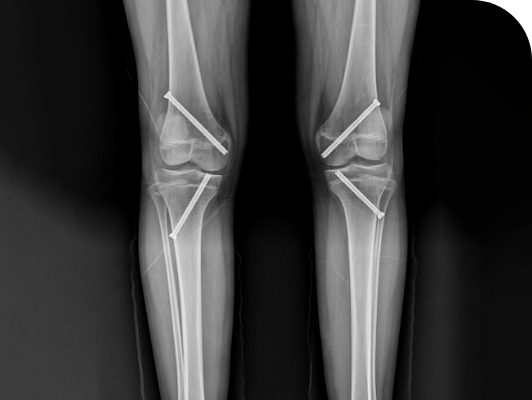

두발로병원의 휜다리 치료, 경피적 성장판 정지술은 성장이 남아있는

아이의 경우 성장판 한쪽에 기구를 이용해 일시적으로 자라지 않게 고정 한 후

반대쪽 성장판을 키워 성장하는 동안 점진적으로 교정되게 하는 수술입니다.

수술 전

교정이 필요한 휜다리

수술 후

나사 못으로 교정한 상태